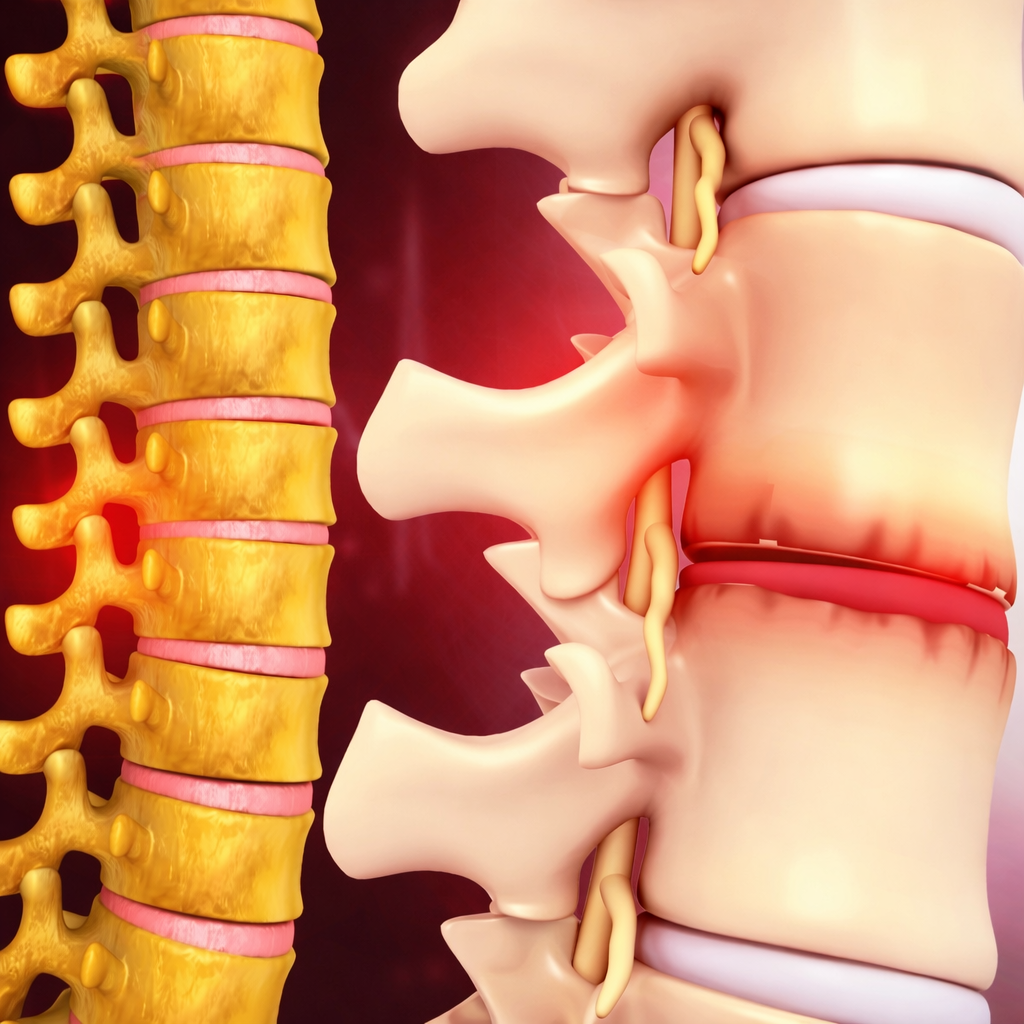

Management of disc-related pain through medications, physiotherapy, lifestyle guidance, or surgical intervention when necessary.

Care for age-related spine degeneration focusing on pain relief, mobility improvement, and functional independence.

Thorough evaluation of spine injuries to determine severity, stability, and appropriate treatment planning.